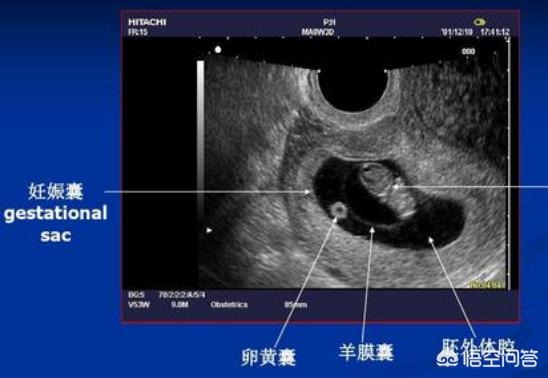

怀孕4周时,受精卵才着床成功; 怀孕5周时,受精卵着床成功后一边快速进行细胞分裂,一边向四周扩展,而这些细胞将会形成羊膜和血管包裹住 卵黄囊,胎儿就是从卵黄囊开始发育的。 在卵黄囊的外面是孕囊,孕囊是原始的胎盘组织。 所以, 一般在怀孕56周,可以做B超看到孕囊和卵黄囊,月经规律的女性,最早在怀孕35天时可以通过阴超看到孕囊; 怀孕67周时,可以通过B超看到胎3 怀孕5周孕囊大小多少是正常的 1、4周:胎儿只有02厘米。 受精卵刚完成着床,羊膜腔才形成,体积很小。 超声还看不清妊娠迹象。 2、5周:胎儿长到04厘米,进入了胚胎期,羊膜腔扩大,原始心血管出现,可有搏动。 B超可看见小胎囊,胎囊约占宫腔不到1胎芽特征 怀孕的第一个月为胎芽期,新生命在此期的成长速度是其一生中最快的。 妊娠第二周末精卵结合,受精后约4天,分裂成细胞团的精卵沿着 输卵管 到达子宫。 第三周,细胞团脱去外膜,为着床作准备。 第四周,胚泡已牢固地植入子宫里。 在这个

1胎囊的大小:怀孕6周时胎囊直径约2厘米,孕10周时约5厘米,孕15个月时直径约2厘米,25个月时约5厘米为正常。 2胚囊:(长)23*(宽)17*(厚)16 mm 是女孩。或35*34*28mm也是女孩。或18*16*8mm也是女孩。33*18mm是男孩,44*mm是男孩。 350D的BC数据:胎囊29*19 mm是男孩。32*mm是女孩。孕囊35*27mm是女孩。 48W的BC 懷孕胎囊的轉變 1、4周, 胎寶寶僅有2mm。 精卵結合剛進行胚胎著床, 羊膜腔才產生, 容積不大。 超聲波還看不清楚懷孕征兆。 2、5周, 胎寶寶長到4mm, 進入了試管胚胎期, 羊膜腔擴張, 初始心腦血管病出現, 可有心搏。 B超可看到小孕囊, 孕囊約占宮腔內不上1/4, 或由此可見胎